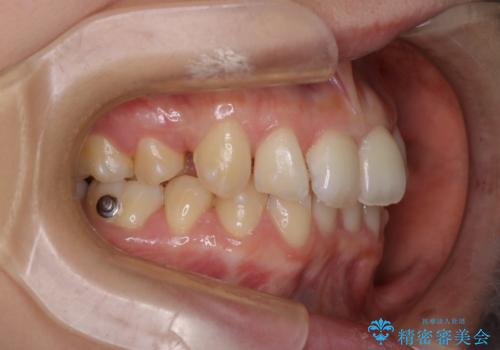

- 患者様は、上下の噛み合わせのバランスが悪く、特に上顎の前歯の突出を気にされて来院されました。診査の結果、下顎の歯並びに合わせて上顎を後方へ移動させる必要があると判断し、上顎の小臼歯2本を抜歯することを提案しました。目立たない矯正を希望されたため、**インビザライン(マウスピース矯正)**を選択。計画的にスペースを作りながら、バランスの取れた歯並びを目指しました。

治療はまず、上顎の小臼歯を2本抜歯し、そのスペースを利用して前歯を後方へ移動させました。インビザラインはアタッチメントを併用し、より効率的に歯を動かせるよう調整。定期的なチェックとアライナーの交換を続け、約3年かけて理想的な歯並びと噛み合わせを実現しました。治療後はリテーナーを使用し、安定した状態を維持。患者様からは「口元がスッキリし、横顔の印象も変わった」と嬉しいお声をいただきました。